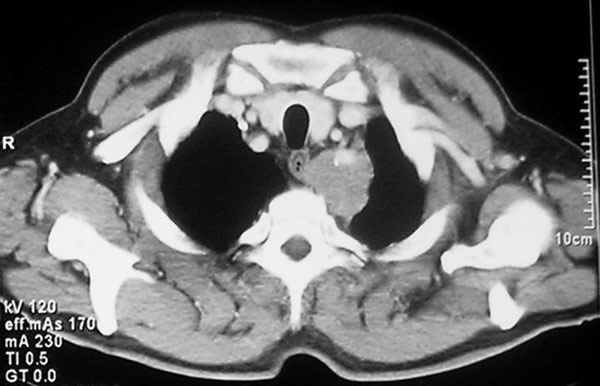

The subclavian artery can usually be dissected through the subadventitial plane (Video 8). Local branches (e.g., the internal mammary artery, thyrocervical trunk, or occasionally the vertebral artery) should be identified and transected if necessary. If the subclavian artery is invaded by tumor (Figure 10), the involved segment can also be resected and reconstructed through a posterior approach (Figure 11). After systemic heparinization, the artery is cross-clamped proximally and distally excluding the invaded segment and revascularized using either an end-to-end anastomosis or, more commonly, the interposition of a polytetrafluoroethylene (PTFE) graft, 6 to 8 mm in diameter (Video 9).

| Figure 10. Chest CT-scan shows the invasion of the subclavian artery by Pancoast tumor. | Figure 11. The invaded artery was resected and replaced by a PTFE graft through a posterior approach. |